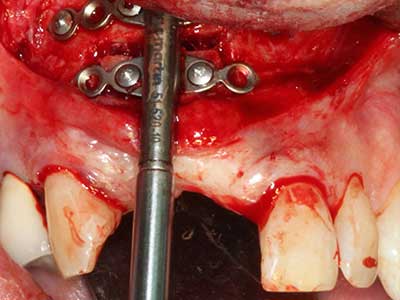

Фиг. 18: Препарация на кортикално покритие с пиезо накрайник за кост (Piezomed, W&H).

Фиг. 19: Хирургичното поле след невролиза и отстраняване на остеотом.

Фиг. 20: Отстраненото костно покритие е поставен отново и фиксиран с винт за остеосинтеза (KLS Martin, Tuttlingen).